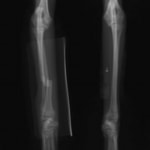

症例:交通事故による椎体脱臼

柴犬:9歳、避妊雌

交通事故直後、胸腰部に激しい疼痛、両後肢に完全麻痺を認め、シェフシェリントン徴候を呈していました。レントゲン検査において、第11-12胸椎間の脱臼が認められました。

脊髄の減圧、脊柱管の再構築・安定化を目的に、片側椎弓切除術およびMatrixMANDIBLE Plateによる椎体固定を実施しました。

隣接椎体を架橋するようにプレートを設置しました。

術後レントゲン写真